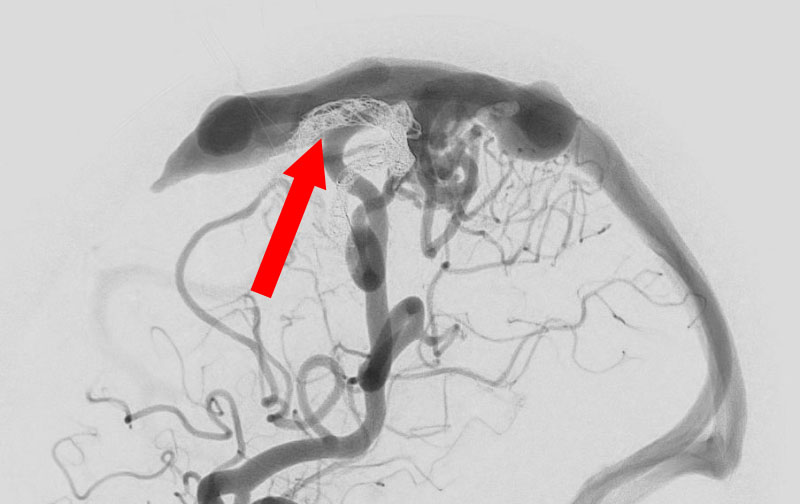

'26年3月

出血性脳動静脈奇形

10代

院内外来

No.1620 手術前

No.1620 手術中

No.1620 手術後